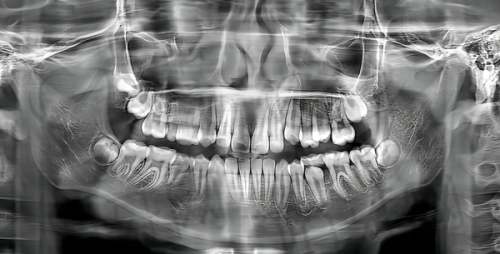

衢州江山可恩口腔门诊部(东方店)配备了数字化设备。数字化设备在口腔诊疗中有诸多优势,比如在口腔检查时,数字化设备能够快速、正确地获取口腔内部的详细信息,生成清晰的图像,医生可以更精细地诊断病情。在治疗过程中,数字化设备可以辅助医生制定更严谨的治疗方案,提高治疗的成功几率和成效。像全景片检查使用数字化设备,能够全方面清晰地展示牙齿和颌骨的情况,为后续的治疗提供有力的依据。